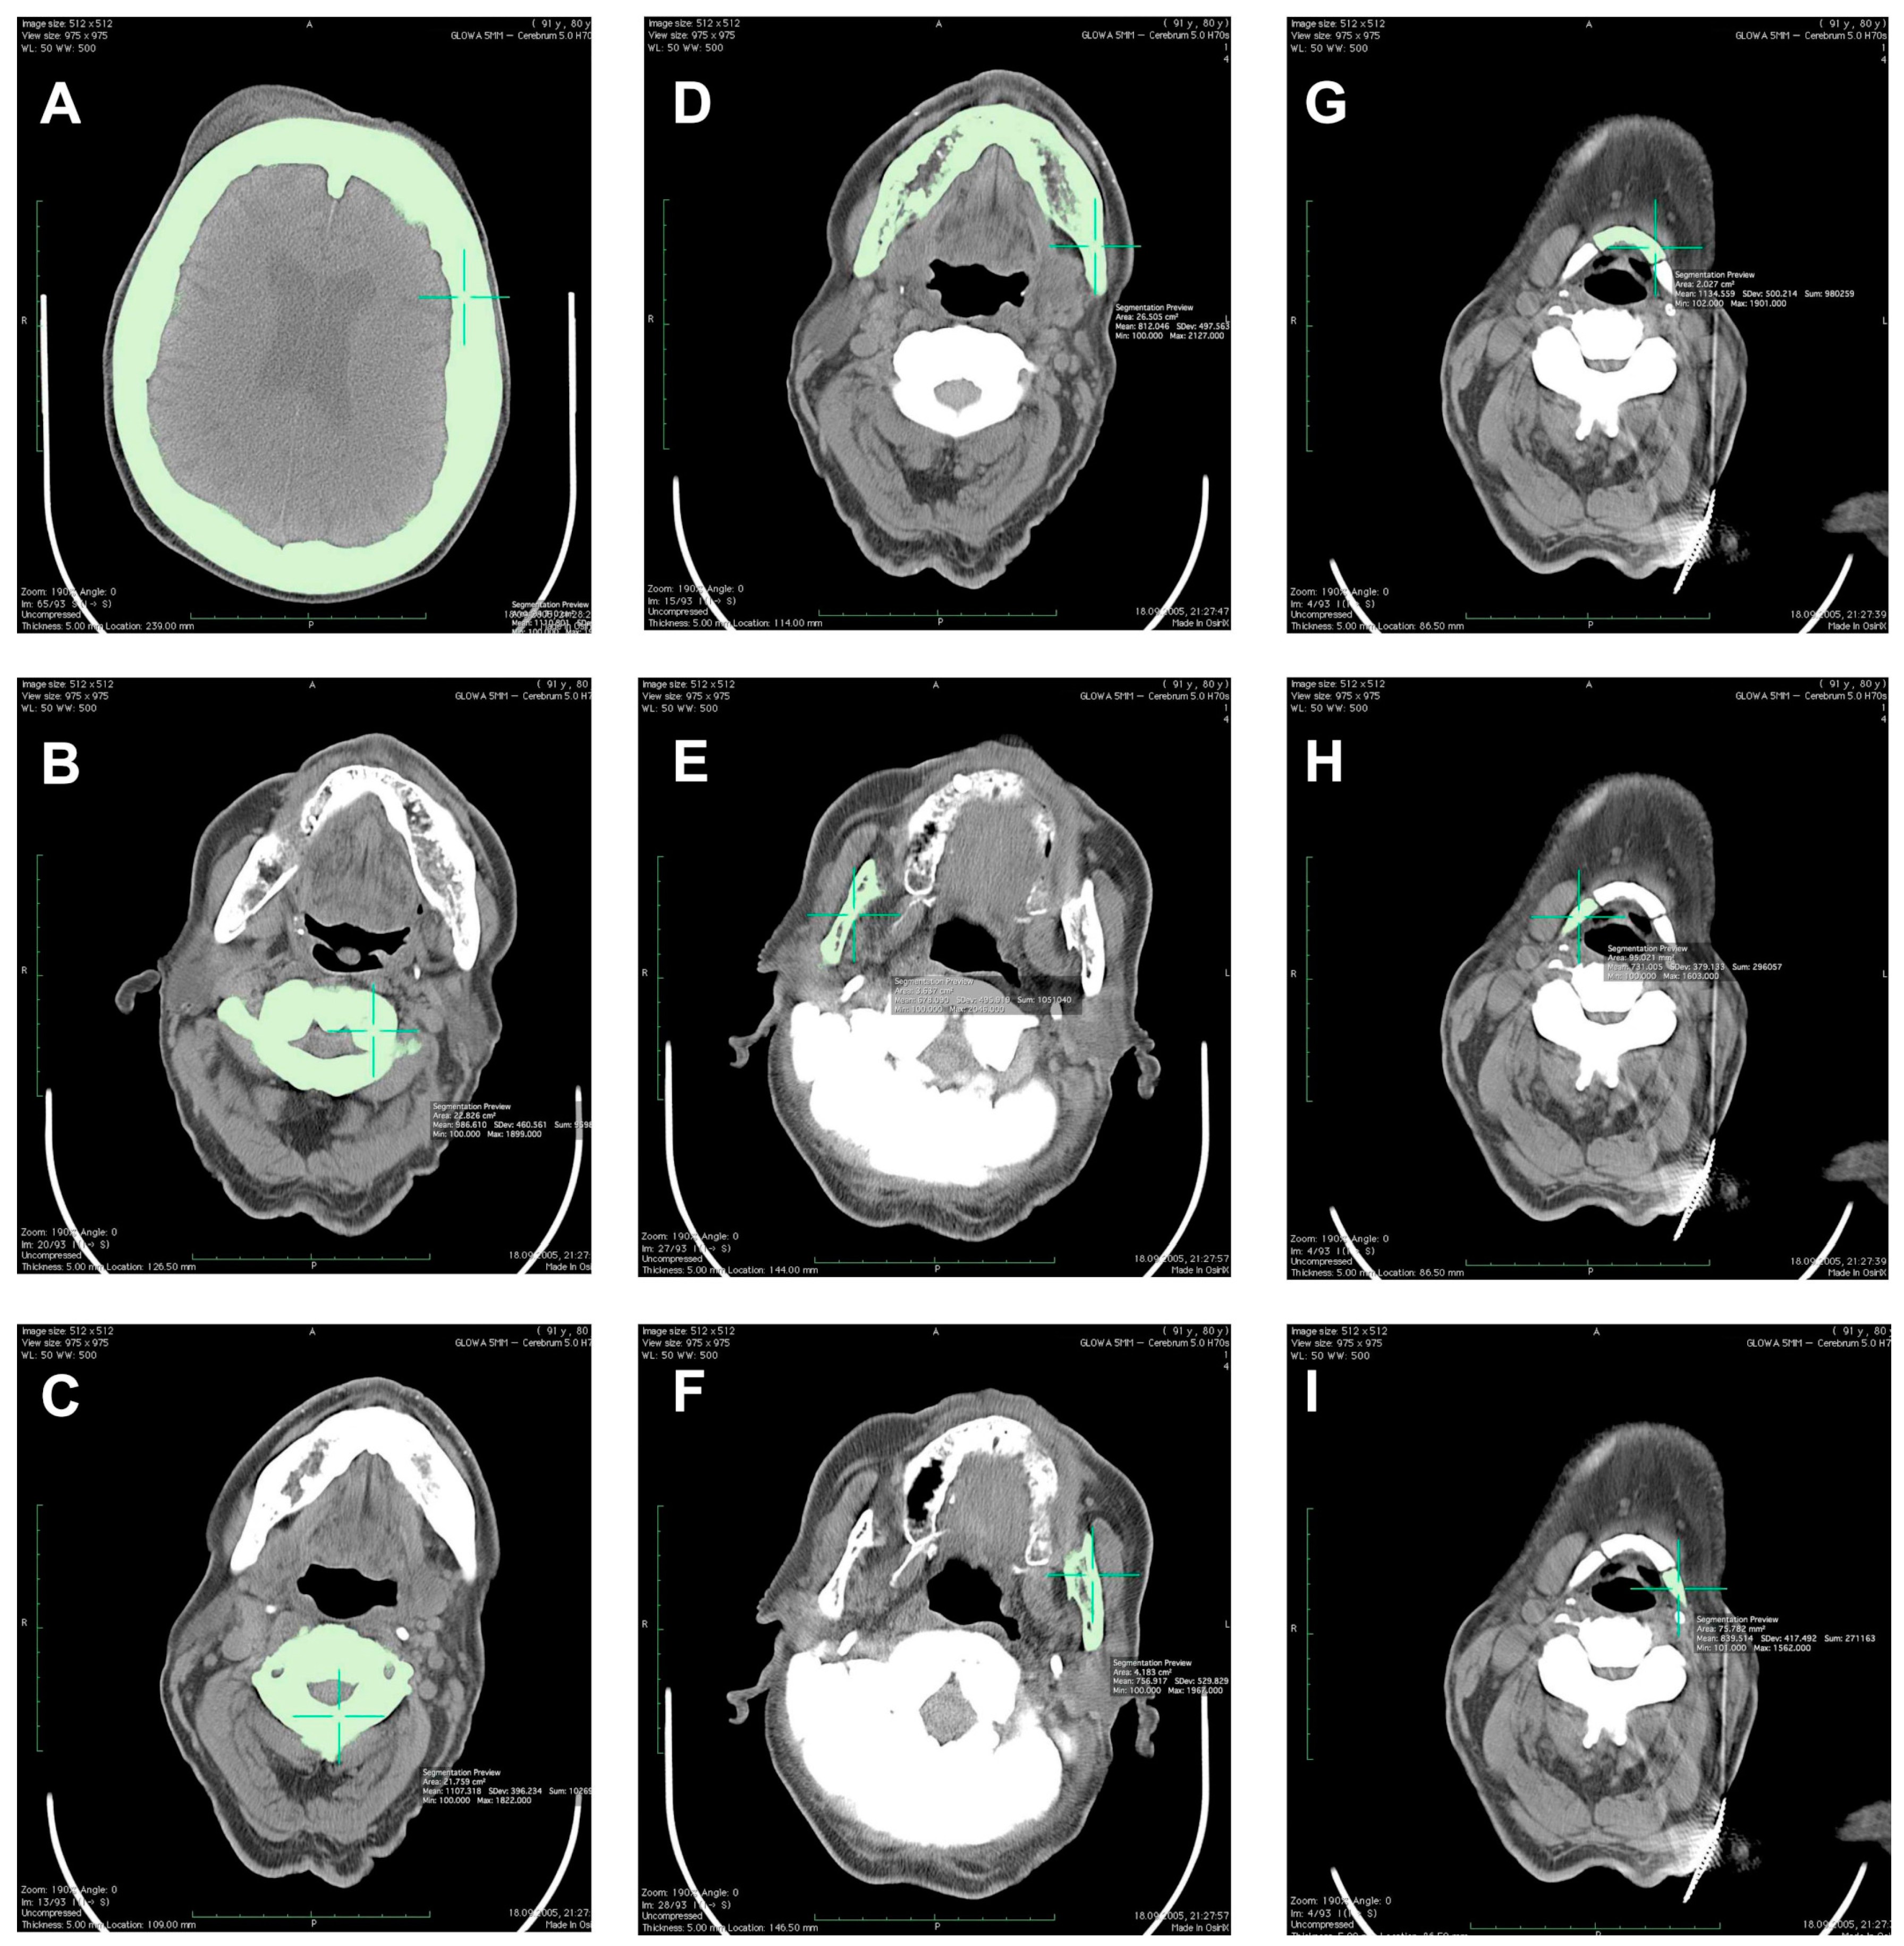

3. Results

| Cranium | |||||

| 50% of cranium height | - | - | - | - | 2.111 |

| Mandible | |||||

| Mandibular body | - | - | - | - | 1.812 |

| Right ramus | - | - | - | - | 1.678 |

| Left ramus | - | - | - | - | 1.757 |

| Hyoid | |||||

| Middle part | - | - | - | - | 2.135 |

| Right part | - | - | - | - | 1.731 |

| Left part | - | - | - | - | 1.840 |